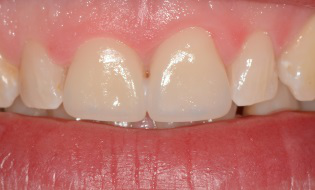

Les 4 incisives maxillaires sont légèrement usées et portent des résines disgracieuses et changées régulièrement. La patiente souhaite un sourire agréable et plaisant en permanence.

Les 4 facettes sont posées en fin d’après-midi.